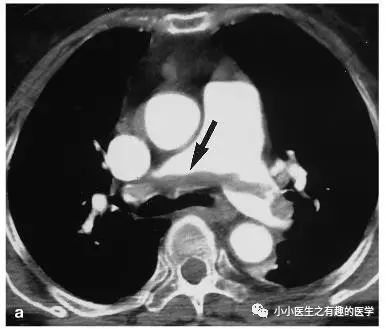

仔细看,有端倪。

增强CT可以核实。